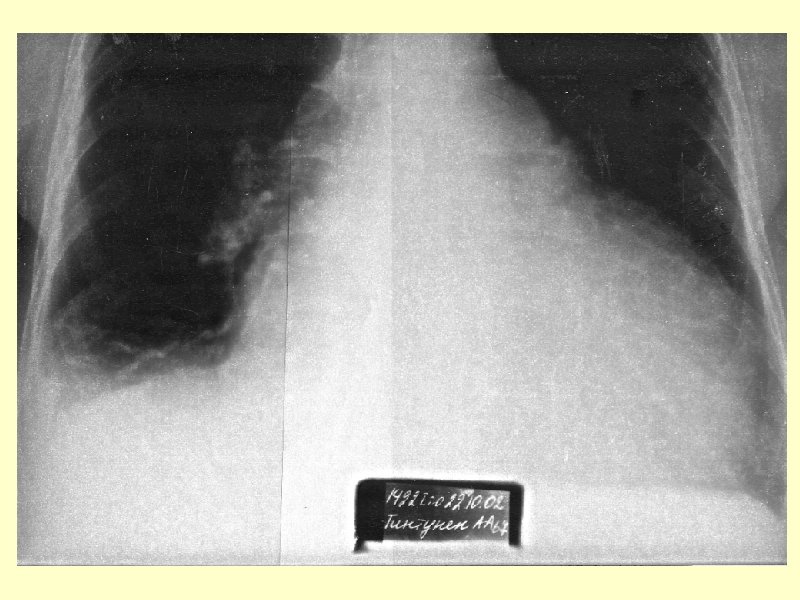

III. Объективные признаки дисфункции сердца Инструментальная диагностика • Рентгенография органов грудной клетки § Кардиомегалия: § ↑ кардиоторакального индекса (более 50%), поперечный размер сердца > 15, 5 см у мужчин и > 14, 5 см у женщин), § Признаки венозного застоя в малом круге кровообращения: § расширение корней, § интерстициальный отек, § образование септальных линий Керли (жидкость в междольковых щелях с одновременным расширением лимфатических сосудов), § жидкость в плевральных полостях (чаще справа).

Острая сердечная недостаточность (отек легких) • Тяжелый респираторный дистресс синдром • Клинические проявления o Одышка, удушье, усиливающееся в горизонтальном положении (ортопноэ) o Сердцебиение o Кашель сухой или с пенистой розоватой мокротой o Беспокойство o Кожные покровы бледные, влажные o При аускультации легких: § многочисленные влажные хрипы § нередко бронхоспазм o На рентгенограмме легких: § Расширение, нечеткость корней легких § Усиление легочного рисунка, особенно в нижних отделах o Насыщение артериальной крови кислородом < 90% до начала терапии